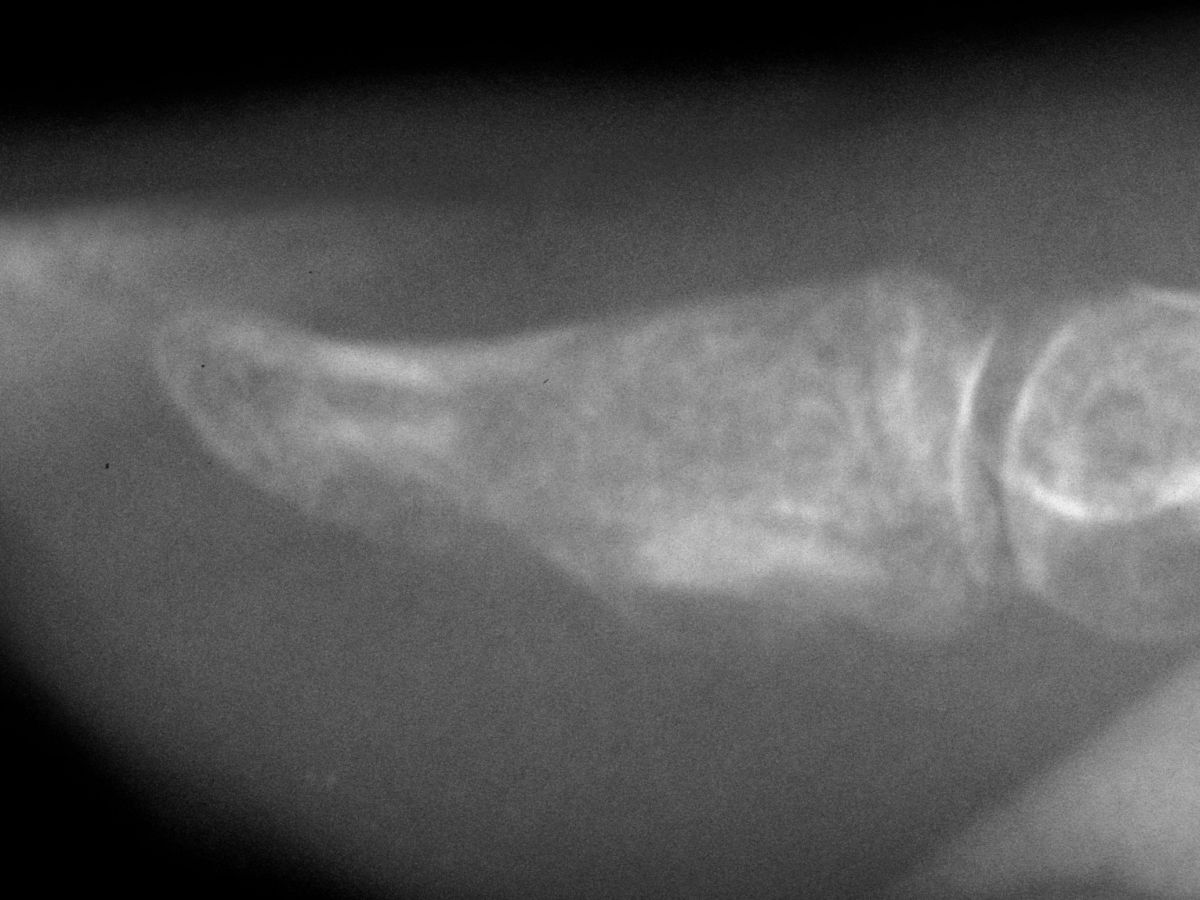

| Case 2. This patient presented months after having "injured" her middle fingertip, feeling that the finger was not normal. Xrays were consistent with an enchondroma and probable dorsal angulation from a healed pathologic fracture. |